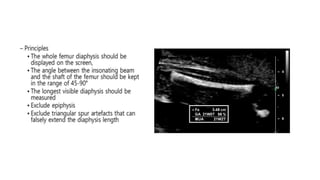

Femoral Length

FL